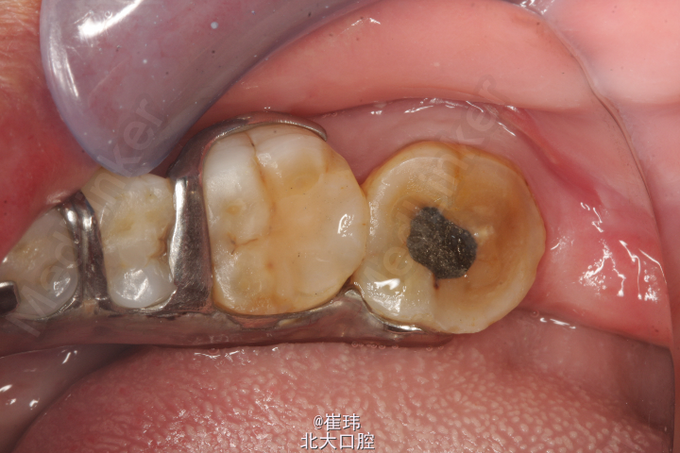

37O :银汞充填体,边缘良好,叩(±),不松,龈未见明显异常。冷测无反应。 36DO : 牙色充填体,边缘良好,叩(-),不松,龈未见明显异常。 X片示37: 充填体达根管口,未见根充影像根尖周未见明显异常 左上后牙固定修复体 27O 探及一深龋洞,色黑,质软,叩痛(+),不松,龈未见明显异常,冷测激发痛。修复科拆除26,27牙冠,拆除牙冠后见近中舌及远中颊合面深大龋洞,探敏感,质软

诊断:慢性牙髓炎急性发作

对于牙疼患者定位要准确,牙髓炎急性发作时常呈放散痛,所以检查时一定不能放过对合牙